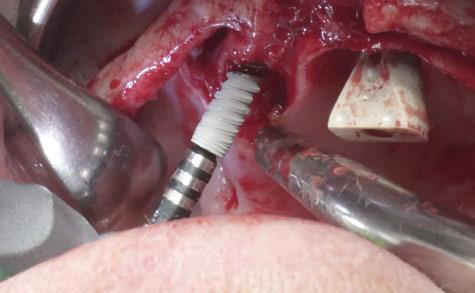

–Implante inmediato en incisivo lateral superior con técnica de «Socket Shield» y acceso vestibular para legrado de la lesión periapical, por el Dr. Ignacio Tormo Jiménez y cols. [106]